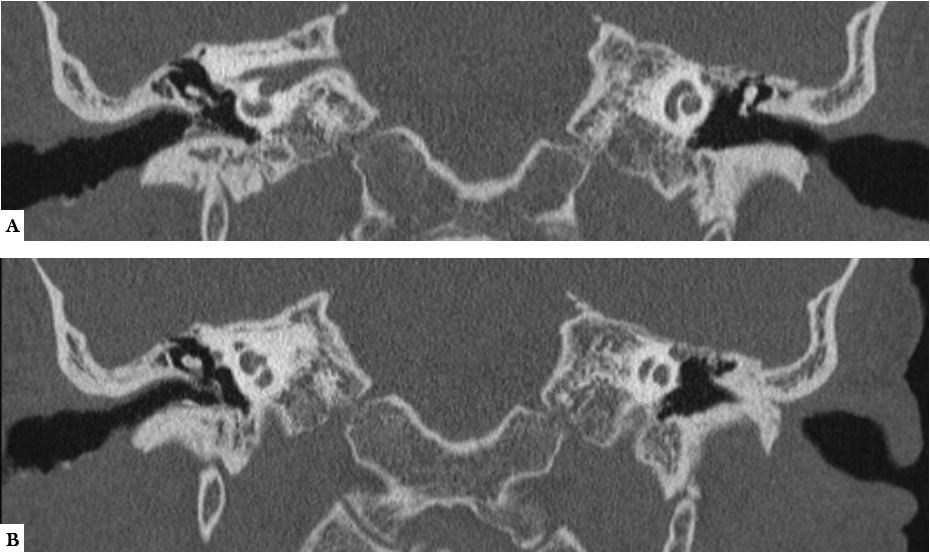

A, B. TC MPR coronal. Engrosamiento leve e irregular de las paredes del CAE y engrosamiento de la membrana timpánica derechas. No ocupación de la caja derecha (existía un discreto aumento de partes blandas en celdillas mastoideas- no mostrado).Oído izquierdo sin alteraciones.